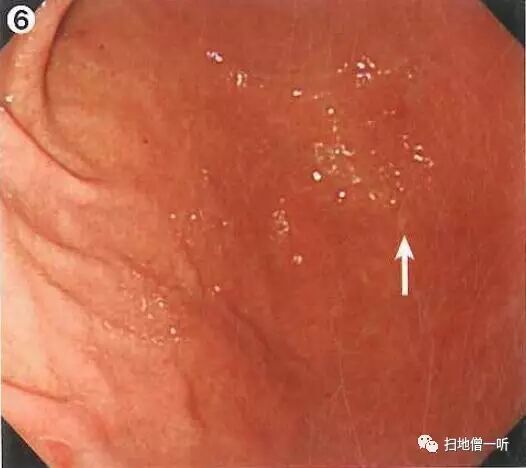

A:病变胃癌在图6。HP阴性胃癌。

背景粘膜无萎缩表现,RAC可见,提示HP未感染。此情况分化癌不多见,警惕未分化癌特别是印戒细胞癌的发生。此病例胃角大弯远景观察下可见一小片状褪色粘膜。

接近观察可见大小约为3mm褪色病变。除了色泽上的变化,其表面无凸凹感。